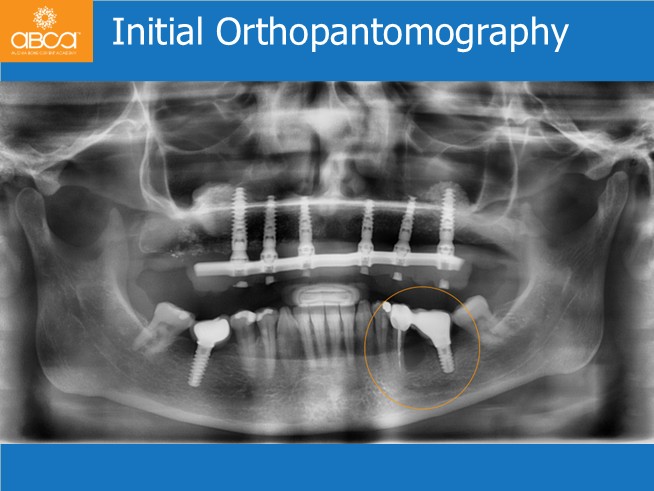

The patient is a 60-year-old healthy woman who complains of pain and bleeding in the area of tooth #35 (20). The oral examination reveals bleeding and a high degree of inflammation on the buccal side of teeth #35 (20) and #36 (19), with a lack of keratinized tissue around tooth #36 (19). A bridge is present and exhibits lateral movement. Complementary examinations show an old bridge connecting a natural tooth #35 (20) to an implant #36 (19), associated with a large cyst and loss of the buccal bone wall at the premolar site, as well as lack of osseointegration of the implant. The patient does not wish to lose the teeth.